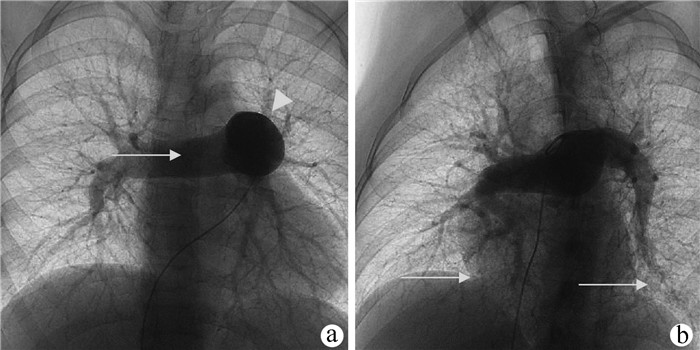

伴肺动脉高压的系统性红斑狼疮患者肝损伤1例报告

李彦霖, 王一川, 吴剑华, 贾佩, 汪瑶, 樊万虎, 刘正稳, 罗静, 张松林, 刘小静

2022, 38(2): 420-422. DOI: 10.3969/j.issn.1001-5256.2022.02.031

摘要(1006) HTML (262) PDF (2037KB)(49)

摘要: